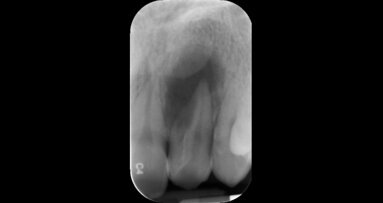

A formação vai abordar, para além de facetas em resina composta, outros tratamentos minimamente invasivos, bem como compreender o enquadramento da estética dentária no contexto da medicina dentária atual. Destina-se a médicos dentistas e estudantes de medicina dentária que tenham gosto e interesse especial pela área da dentisteria estética e reabilitação oral e estará dividido em componente teórica e componente prática (hands-on).

Joana Couto menciona que as “facetas em resina composta têm demonstrado ser uma excelente solução na medicina dentária estética, sendo um tratamento estético simples, de fácil reparação, conservador e económico”. A formadora convida à participação no curso, reforçando que este irá ser uma experiência muito útil à prática clínica dos formandos.